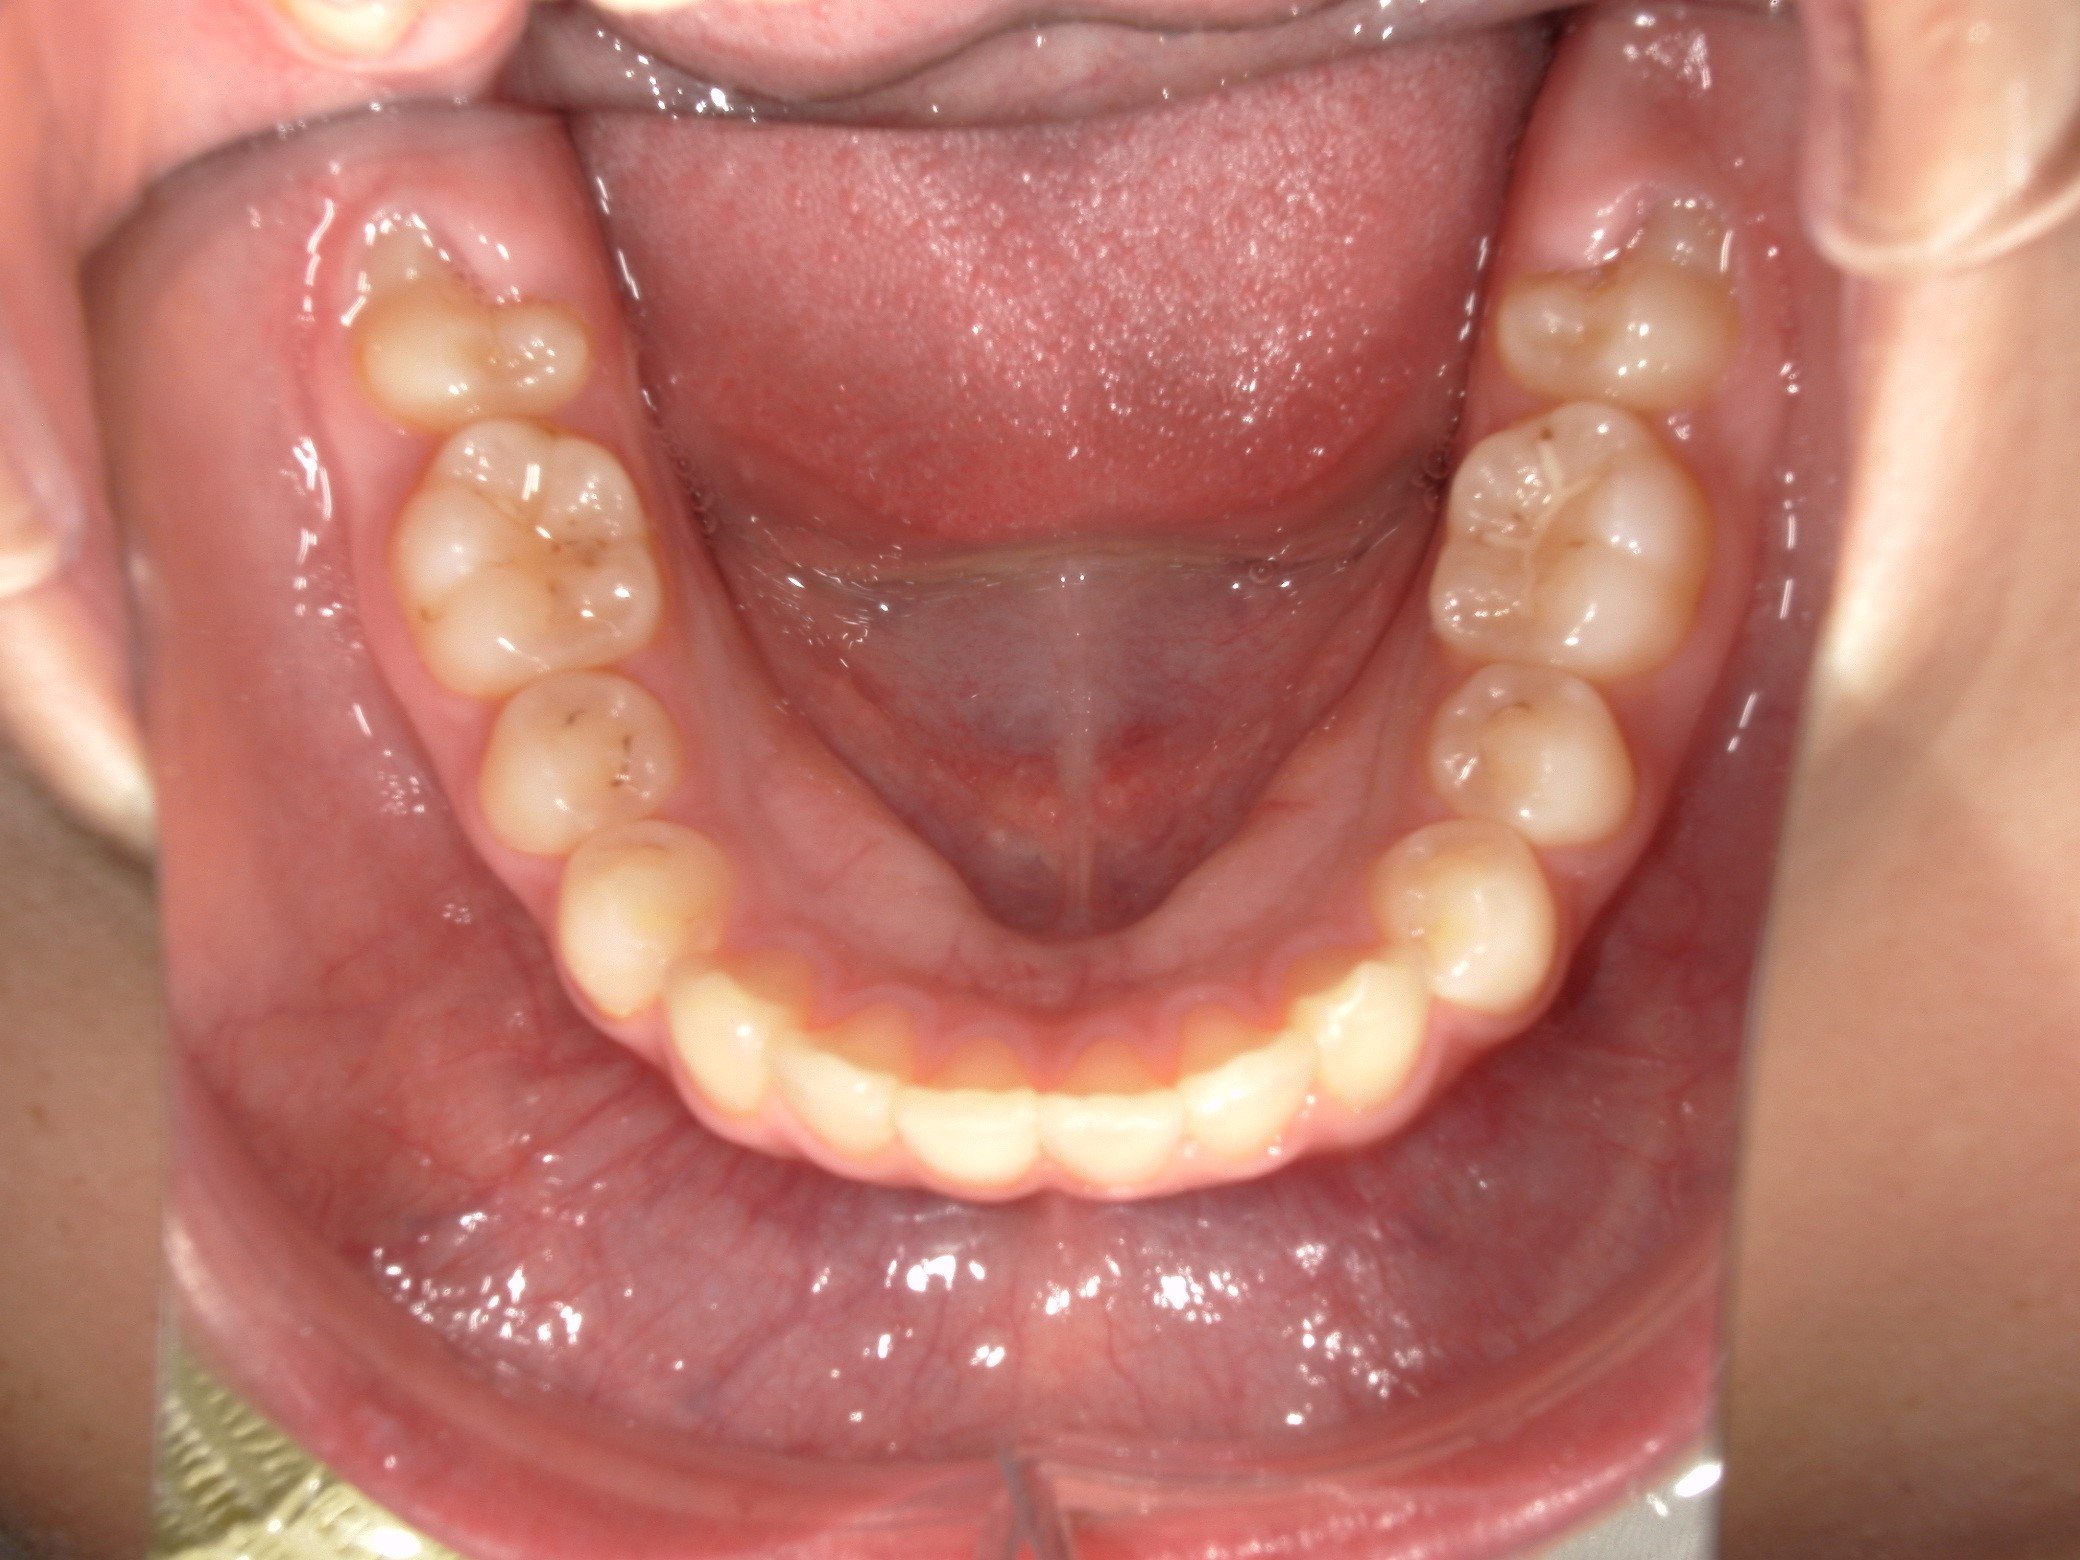

大きな問題点: 本来なら生えきっているはずの下顎左右の第二大臼歯(一番奥の7番目の歯)が、萌出時期を過ぎても歯ぐきに埋まったままの「半萌出状態」となっていました。

③総合歯科ならではの処置

下顎の抜歯予定歯(5番)に対して、あえて事前に根管治療(神経の処置)を行い、治療の「途中の最適なタイミング」で抜歯する特殊なプロセスを採用しました。

③装置装着1年1か月後:こだわりのタイミングでの抜歯

この段階で、事前に根管治療を終えていた下顎左右の5番を抜歯しました。 一般的な矯正では治療開始前に抜歯しますが、本症例では「先に噛み合わせの高さを改善することを優先した」ため、あえてこの時期に抜歯を行いました。

・スペース不足で生えてこなかった下顎の7番も、正常な位置へと誘導することができました。